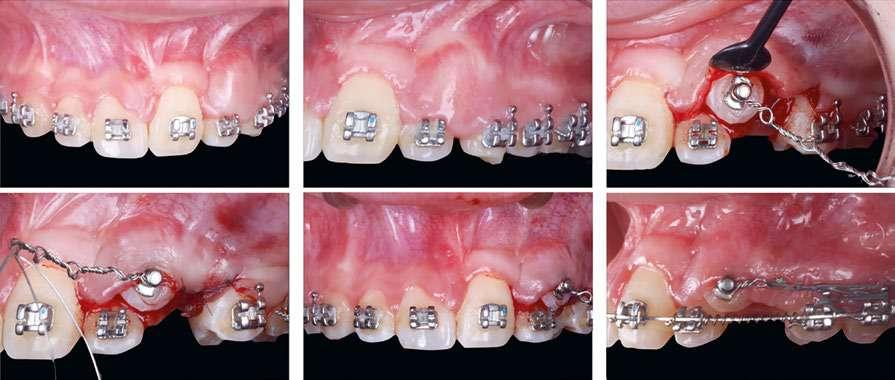

En la exploración clínica observamos recesiones gingivales múltiples en maxilar superior combinado con erosión de la encía y ligero desgaste cervical que borra la línea amelocementaria (Fig. 1). El sondaje periodontal en todos los dientes fue inferior o igual a 3 mm y no se detectaron puntos de sangrado al sondaje. Los dientes 1.3 y 2.3 mostraron ≤ 1 mm de encía queratinizada apical a la recesión. Cabe también destacar la rotación del incisivo lateral superior derecho (1.2). El principal factor etiológico de sospecha en este caso fue el cepillado agresivo.

Después de un detallado análisis y valoración de las alternativas terapéuticas, se planificaron 2 procedimientos quirúrgicos mediante colgajos de avance coronal con acceso lateral y sin descargas para el tratamiento de las recesiones del maxilar superior (Fig. 2) (7-9).

A continuación procederemos a describir el paso a paso del tratamiento quirúrgico de las recesiones (Figs. 2 a 7). Ambos procedimientos quirúrgicos se realizaron bajo anestesia local y sedación consciente por vía endovenosa y con un tiempo de descanso para el paciente entre procedimientos de 1 mes y medio. En este caso, el eje de rotación fueron los caninos en ambos lados y todas las incisiones para-marginales oblicuas (líneas punteadas en rojo) se realizaron hacia estos dientes (Fig. 2).

Figura 1: Situación inicial. Obsérvese la recesión gingival profunda en 1.3 y 2.3, así como la erosión gingival y el borrado de la línea amelocementaria debido al cepillado agresivo.

caso clínicoCIRUGÍA BUCAL

los dientes 1.5, 2.4 y 2.5 para garantizar una correcta adaptación del

Figura 2. Planificación quirúrgica.

Figura 4. Diseño de las incisiones y del colgajo. Nótese la creación de una “falsa recesión” en

colgajo al finalizar el avance coronal.

Figura 3. Situación clínica el día de la intervención quirúrgica.

Figura 5. Colgajo elevado “Split-Full-Split” y fijación de los injertos de tejido conectivo con suturas 7/0 reabsorbibles (PGA).

Figura 7. Post-operatorio y excelente curación 7 días después de la cirugía.

Figura 6. Avance coronal sin tensión y sutura del colgajo mediante puntos “sling” con sutura 6/0 reabsorbible (PGA).

Cada incisión oblicua debía permitir el correcto movimiento lateral y coronal de la punta de la papila quirúrgica hacia su papila anatómica correspondiente. Las incisiones para-marginales oblicuas debían conectar la parte más apical de la recesión con un punto final ubicado en la base de la papila de los dientes vecinos. La altura de este punto final se midió desde la punta de la papila y corresponde a la altura de la recesión + 1 mm. Adicionalmente, para permitir llevar a cabo un colgajo sin descargas, conseguir el suficiente avance coronal a nivel de 2.3, así como una buena adaptación del colgajo en premolares, se realizaron “falsas recesiones” (10) a nivel de 2.4 y 2.5 (Fig. 4). Finalmente, y de acuerdo con los estudios de Stefanini y colaboradores (9), se planificó aplicar el injerto de tejido conectivo (ITC) de manera sitio-específica en los dientes 1.3 y 2.3 debido a la presencia de una banda de encía queratinizada apical a la recesión ≤ 1 mm (Fig. 2 y 5).

La elevación y preparación del colgajo incluyó un abordaje “split-full-split”. En primer lugar, se elevaron las papilas quirúrgicas a espesor parcial utilizando hojas de bisturí 15C. Luego, se realizó la elevación a espesor total en el tejido queratinizado apical a la recesión para exponer aproximadamente 3 mm de hueso apical a la dehiscencia ósea (se puede ver el área de exposición ósea apical a las recesiones) (Fig. 5).

Finalmente, se realizaron incisiones profundas y superficiales para disecar la porción apical del colgajo. La incisión profunda se hizo paralela al hueso en dirección apical para desprender las inserciones musculares del periostio, mientras que la incisión superficial se realizó paralela a la mucosa de revestimiento para liberar el epitelio del tejido conectivo y de las inserciones musculares.